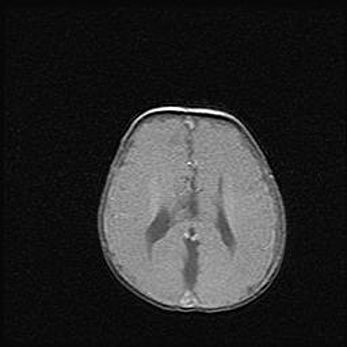

Открытая гидроцефалия.

Возраст: 9 месяцев 12 дней

Вес: 6800 г

Пол: мужской

Окружность головы: 41,5 см

Срок гестации: 28 недель

Гидроцефалия головного мозга у новорожденных имеет характерный признак: опережающий рост окружности головы приводит к визуально хорошо определяемой гидроцефальной форме сильно увеличенного в объёме черепа. Детские неврологи определяют следующие симптомы гидроцефалии у грудничков: выбухающий напряжённый родничок, частое запрокидывание головы, смещение глазных яблок к низу.